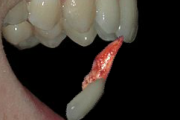

Krooni murd